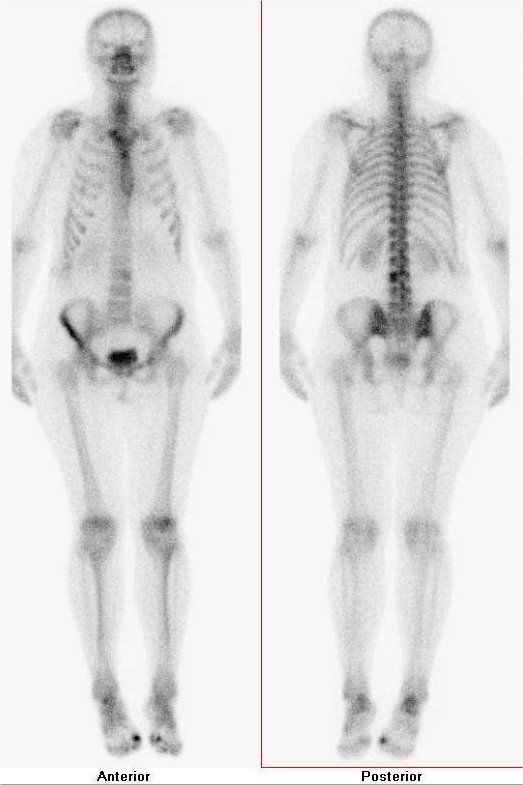

/ Obr. č. 1: Celotělová scintigrafie skeletu v přední a zadní projekci s nálezem zvýšené akumulace radiofarmaka ve střední třetině bederní páteře,

dále v I. metatarsofalangeálním skloubení oboustranně, v pravém talocrurálním skloubení a v patních kostech.

Po aplikaci 700 MBq 99mTc-oxidronátu (přípravek TechneScan HDP firmy Mallinckrodt Medical) byla za 2 hodiny provedena celotělová scintigrafie skeletu na dvoudetektorové tomografické kameře Symbia T2 firmy Siemens, kde byly popsány okrsky zvýšené osteoblastické aktivity ve střední třetině bederní páteře, dále v I. metatarsofalangeálním skloubení oboustranně, v pravém talocrurálním skloubení a v patních kostech. Vzhledem k nálezu v oblasti bederní páteře bylo indikováno doplnění cílené tomografie páteře (SPECT) s CT, na kterém se okrsek zvýšené akumulace radiofarmaka promítal do úrovně těla obratle L3 dorzolaterálně vlevo, kde byla v CT obraze patrná léze s prořídlou kostní trámčinou s drobnými dutinami. Nález odpovídal již dříve popsanému hemangiomu obratlového těla.